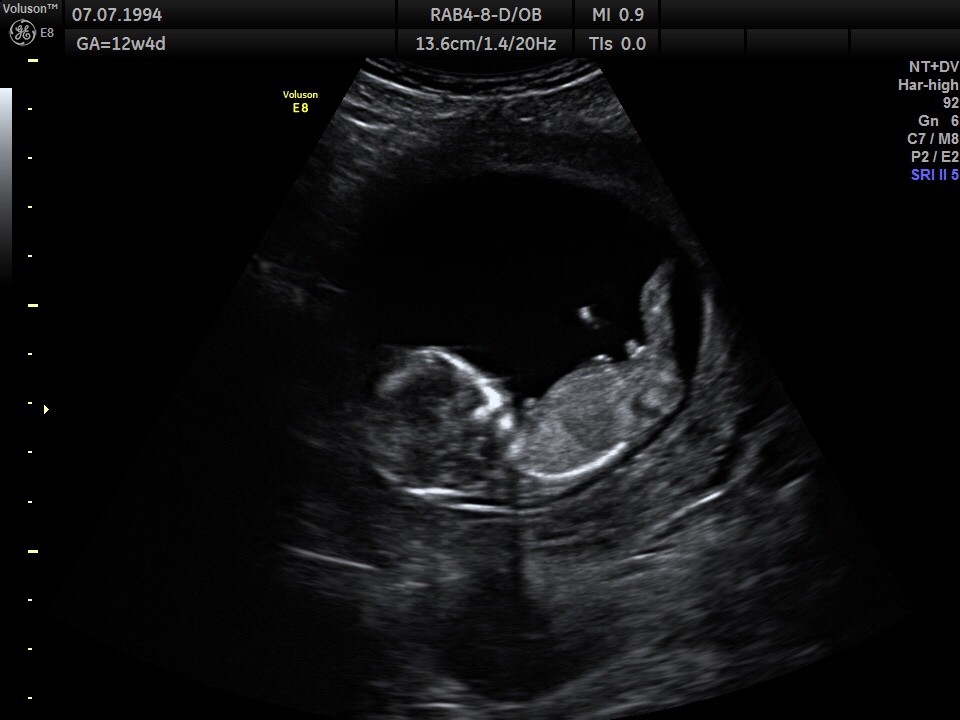

Mi w 1 ciąży lekarz też w 12+5 powiedział że na 95% chłopak. Jeśli się zna to rozpozna różnicę w kacie nachylenia.Przecież w tym tygodniu nie ma narządów rozrodczych tylko wyrostki płciowe.

Nie dane mi nigdy było zobaczenie na żywo „wyrostka” na usg u dziewczynki, ale generalnie na etapie 13 tc żaden mój chłopiec nie zostawiał wątpliwości Zobacz załącznik 850302